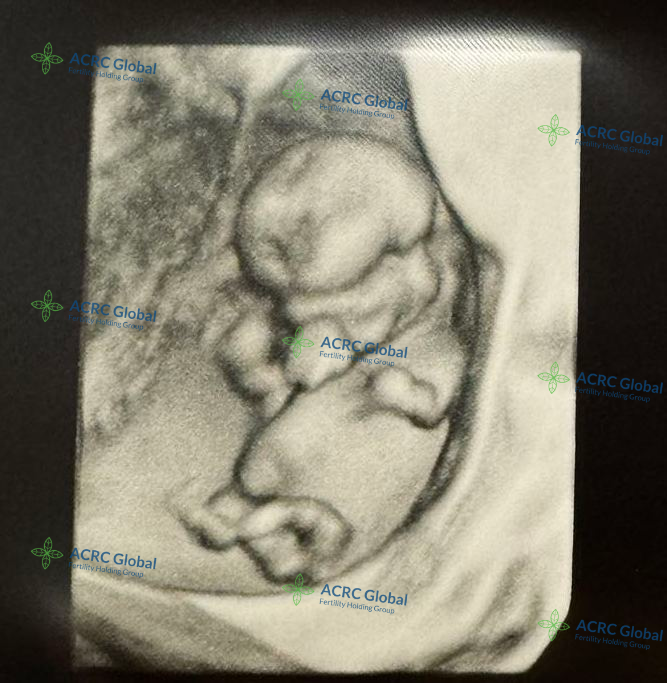

来自伊利诺伊州的爱妈C的第二次孕期旅程也进展顺利,胎宝宝已经进入11周阶段。在这个时候,宝宝已经完成了胚胎期的发育,进入胎儿期,逐渐变得更加稳定。

胎宝宝大约有5厘米长,体重约为7克左右

宝宝的器官和系统正在快速发育,心脏已经开始跳动,神经系统也在形成,B超显示宝宝的手指和脚趾已经开始分开,外耳、鼻子和嘴巴的结构也变得更加清晰。虽然胎宝宝还很小,但此时的他已经开始在羊水中轻微移动,只不过爱妈还感受不到这种活动。